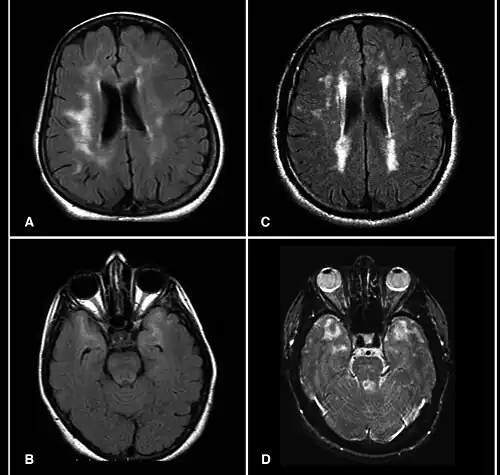

CADASIL is an inherited disorder caused by mutations in the NOTCH3 gene located on chromosome 19.[19] NOTCH3 codes for a transmembrane protein whose function is not well-known. However, the mutation causes accumulation of this protein within small to medium-sized blood vessels.[19] This disease often presents in early adulthood with migraines, stroke, mood disturbances, and cognitive deterioration. MRI shows white matter changes in the brain and also signs of repeated strokes. The diagnosis can be confirmed by gene testing.[20]

MRI demonstrating white matter changes in the brain of patients with CADASIL

MRI demonstrating white matter changes in the brain of patients with CADASIL -

Brain infarct

Brain infarct